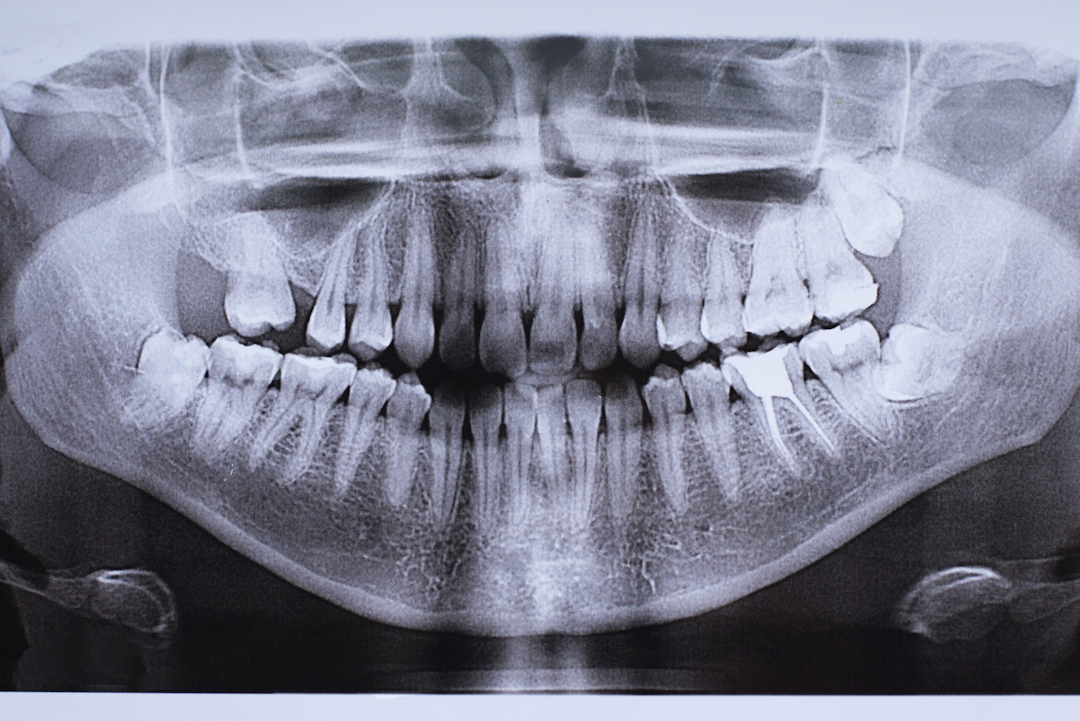

Рентгенография – основной метод диагностики проблем с зубом мудрости. Прицельный снимок показывает состояние одного зуба, положение его корней и наличие воспаления. Процедура занимает 2-3 минуты и абсолютно безболезненна.

Ортопантомография (панорамный снимок) дает полную картину обеих челюстей. На нем видны все зубы мудрости, их положение относительно соседних зубов и нервов. Этот метод особенно важен перед планированием удаления.

В сложных случаях назначают компьютерную томографию. Трехмерное изображение позволяет увидеть точное положение корней, их близость к нервам и гайморовой пазухе. КТ необходима при планировании сложного удаления дистопированного зуба.

Диагностика помогает врачу принять обоснованное решение – лечить или удалять. Она также предотвращает осложнения во время операции и позволяет спланировать оптимальный метод вмешательства.